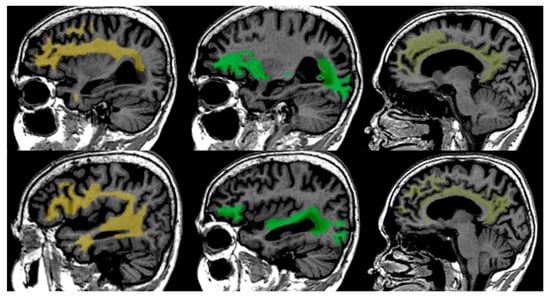

FA changes and complexity of white matter changes in Cognitive Decline. The observed variability in fractional anisotropy (FA) across different cognitive impairment levels shows the relationship between white matter integrity and cognitive decline. However, the relationship between FA and cognitive decline is complex, as it is influenced by several factors, including the extent of fiber alignment, the presence of structural damage, and the differential vulnerability of various white matter tracts [27,28].As white matter damage progresses, FA values typically decrease, reflecting a loss of fibre coherence and increased isotropic diffusion. However, in the presence of partially preserved tracts or compensatory mechanisms may sustain higher FA values in certain regions, even in the face of cognitive decline [29,30], see Figure 6.

Figure 6.

Concept of fractional anisotropy (FA) and its implications for white matter integrity analysis using FA values. (A)—three nerve bundles (blue, brown, yellow) representing moderate FA value, where ellipsoid would be elongated, but not as much as in panel (B), signifying moderate FA values. This indicates that water molecules predominantly diffuse along the direction of the fibers, but with some degree of diffusion in other directions. (B)—two nerve bundles (brown and yellow) intact, grey nerve bundle damaged, resulting in increased isotropic diffusion and higher FA value. (C)—all nerve bundles are depicted in grey, indicating significant loss of organization and alignment, low FA value, representing severe white matter damage and disorganization, typically associated with significant white matter damage and advanced neurodegenerative conditions.

This complexity highlights the need to consider FA alongside other biomarkers to fully understand white matter changes in cognitive decline.